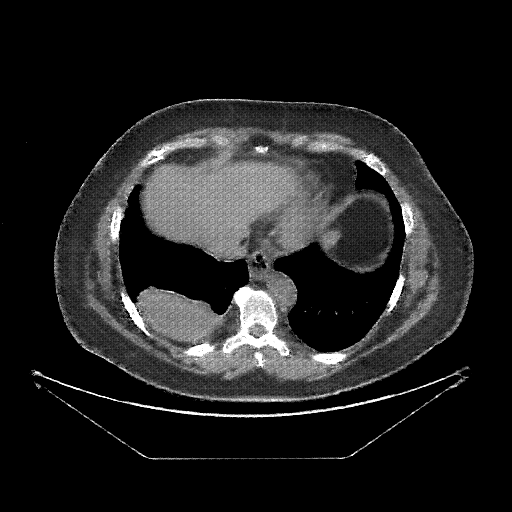

Image Grid

4Γ—3 grid: Rows show different image types (Original NATIVE, Reconstructed NATIVE, Original VENOUS, Generated VENOUS), Columns show windowing techniques (No Window, Lung Window, Mediastinum Window)

Original NATIVE CT scan (input)

Full window (WL 1023.5, WW 4095 β†’ Low βˆ’1024, High +3071)

Original VENOUS CT scan

Generated VENOUS CT scan (A→B translation)